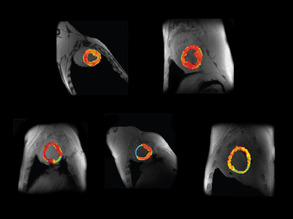

Weak Hearted